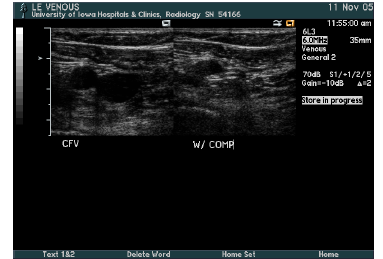

what is this?

trans CFV proximal to GS junction